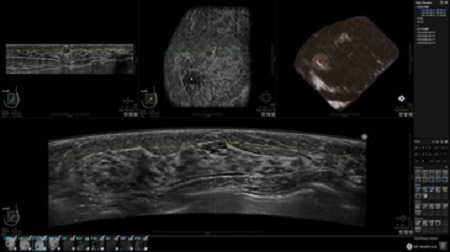

УЗИ-аппарат GE INVENIA ABUS позволяет проводить максимально операторонезависимые процедуры, что значительно снижает риск неправильной постановки диагноза и сопутствующие издержки на обработку информации. Система готовит отчет в течение 3-х минут после сканирования, это безусловное преимущество по сравнению с обычным УЗИ сканером.

• Получение объемных 3D изображений с возможностью покадрового просмотра

• Получение изображений в поперечной плоскости (в реальном времени) и в коронарной плоскости (статическая, для указания нахождения соска)

• Отображение объемных 3D ультразвуковых изображений, которые состоят из традиционных поперечных и воссозданных коронарных и сагиттальных проекций

• Возможность отображения полного 3D изображения

• Стандартизованная ориентация изображения: «толстый срез» в коронарной плоскости; поперечная; сагиттальная плоскость; радиальный и антирадиальный поворот изображения; просмотр исключительно области интереса

• 360 ° APC - отображение области по «любой точке компаса»